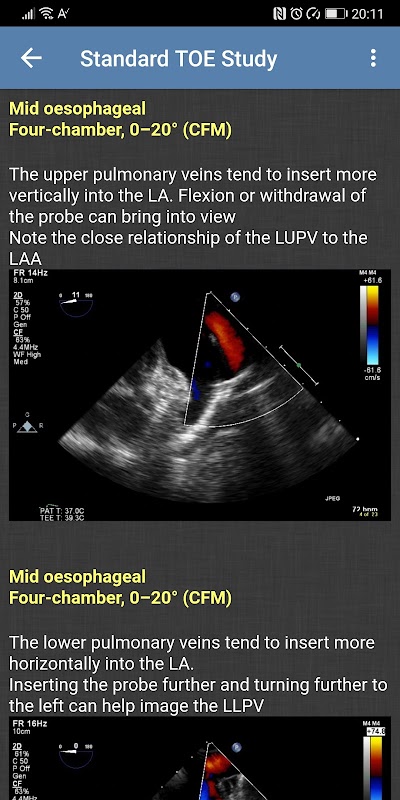

- मानक टीओई अध्ययन